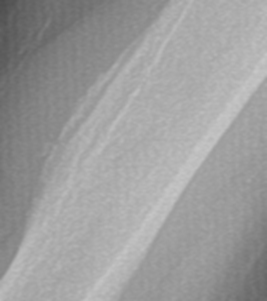

3. Prominent Soleal Line

Figure 4 demonstrates prominent ossification that obliquely traverses the proximal tibia at the origin of the soleus muscle. Figure 5 demonstrates a thick osseous protrusion along the posterior tibia. This normal variant can be mistaken for an aggressive periosteal reaction or pathologic heterotopic ossification. But the anatomic orientation of the ossification along the soleal insertion and no involvment of the underlying bone should allow the clinician to easily identify this variant. This normal viariant has also been termed tibial pseudoperiostitis or tibial tug lesion.